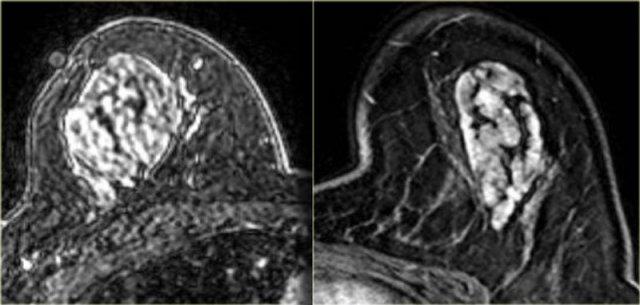

Bên trái là ví dụ điển hình của u xơ tuyến: một tổn thương hình tròn, bờ nhẵn

với một số vùng đen hoặc xám ở bên trong, đó là các vách ngăn không ngấm thuốc.

Tổn thương này có đường cong động học loại 1.

Ngoài cùng bên trái là một ví dụ khác về u xơ tuyến với các vách ngăn không ngấm thuốc rõ ràng.

Các vách ngăn này cũng có thể quan sát thấy trên tiêu bản đại thể bệnh lý.